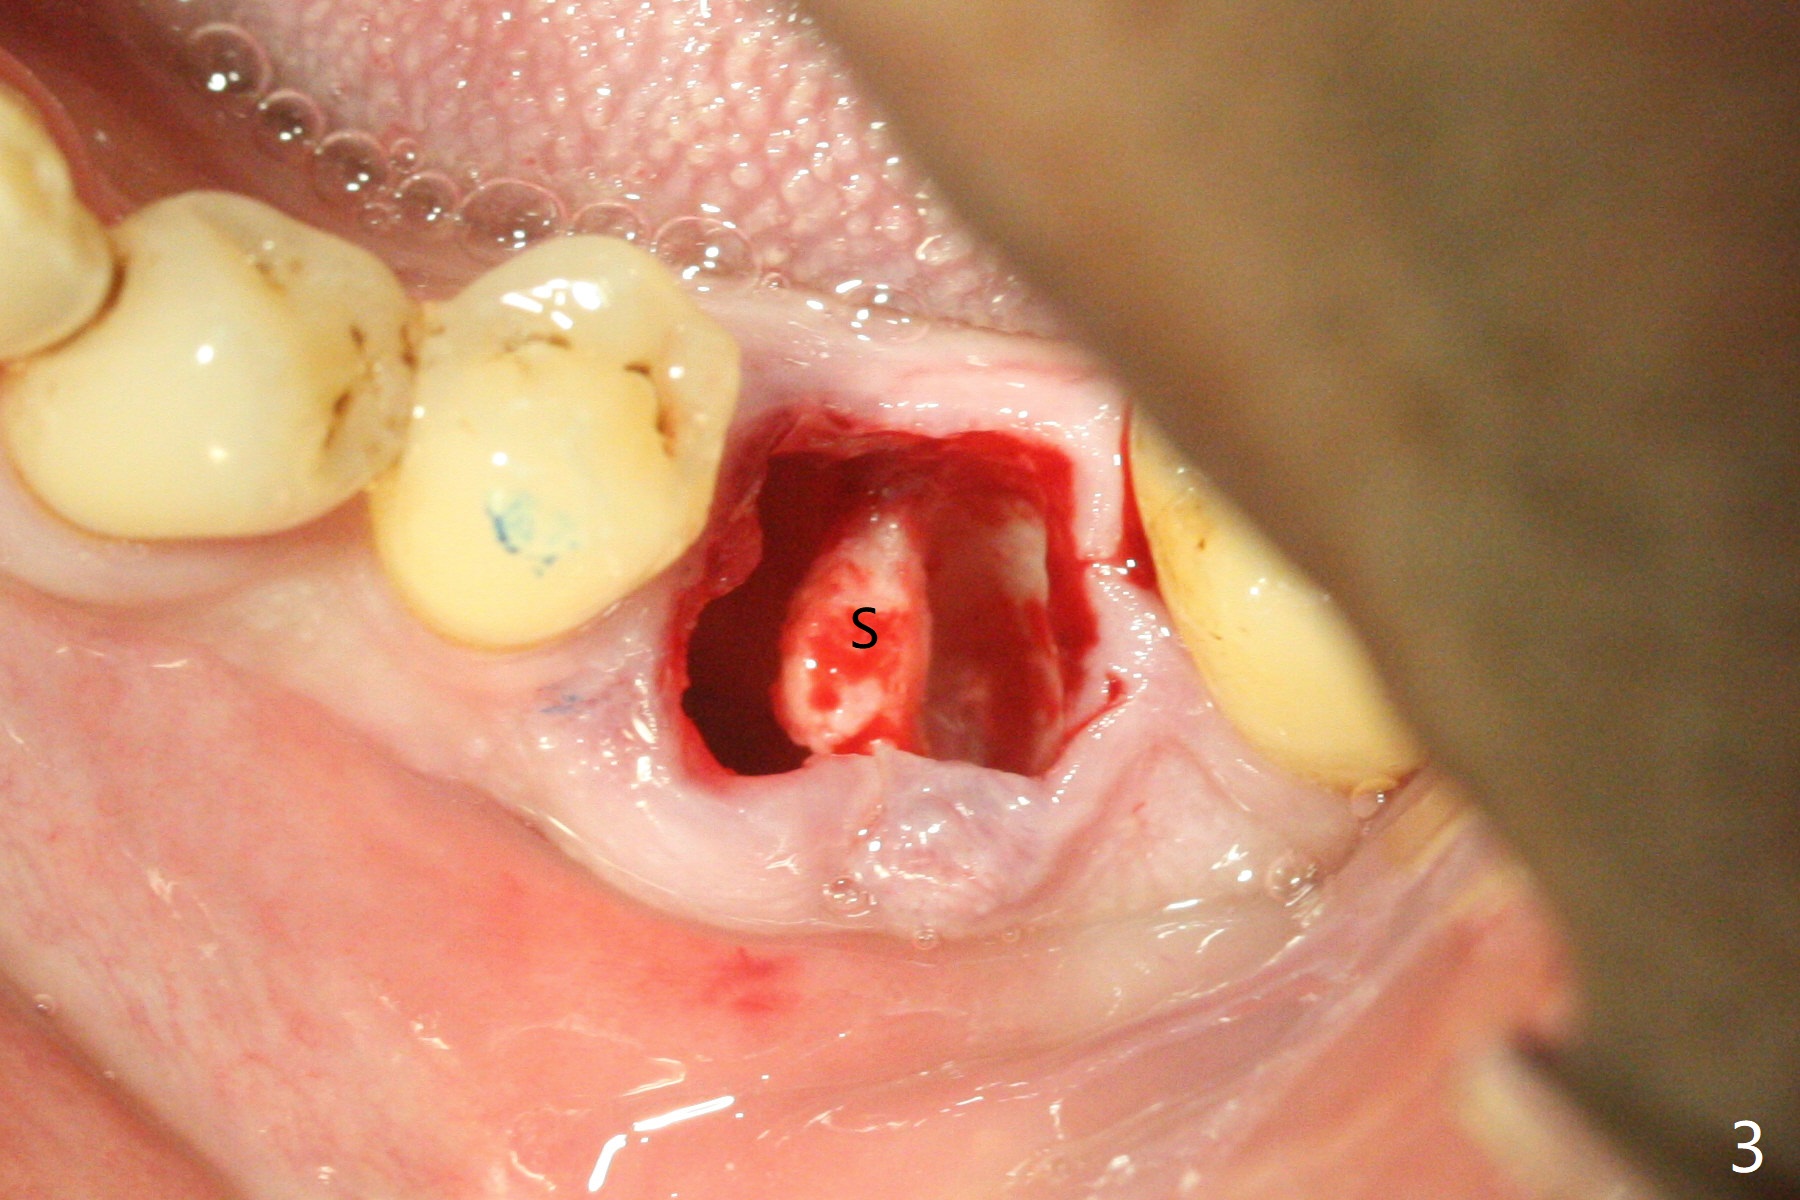

When the patient returns for #15 comp, the bone resorption and swelling at #19 are worse than those 3 years ago (Fig.1,2). After debridement, the mesial socket is large, while the septum is thin, irregular and with undercut (Fig.3). It seems difficult to obtain primary stability for an immediate implant. Vanilla bone and cortical bone hydrated with GEM21 S are placed for socket preservation (Fig.4,5), followed by 12x12 mm BioXclude and 4/0 PGA. In fact the bone height is limited for an immediate implant (Fig.6 (5x10 mm)). There is not enough bone in the septum for primary stability (Fig.7 (cross section of 3D image; L: lingual)). The socket heals 16 days postop (Fig.8). It appears that the granulation tissue is covered by a thin layer of granulation tissue (Fig.9 *), while the membrane remains in place (M). In fact the bone graft remains in the soft tissue zone as well as the hard tissue one (Fig.10). In spite of no apparent loss of bone graft (Fig.4,10), the graft seems to shrink in height 3.5 months postop (Fig.11), while the crest decreases (compare Fig.1 and 11). The keratinized gingiva is wide, but the alveolus reduces in width (Fig.12). The buccal crestal bone is lost 3.5 months postop (Fig.13).